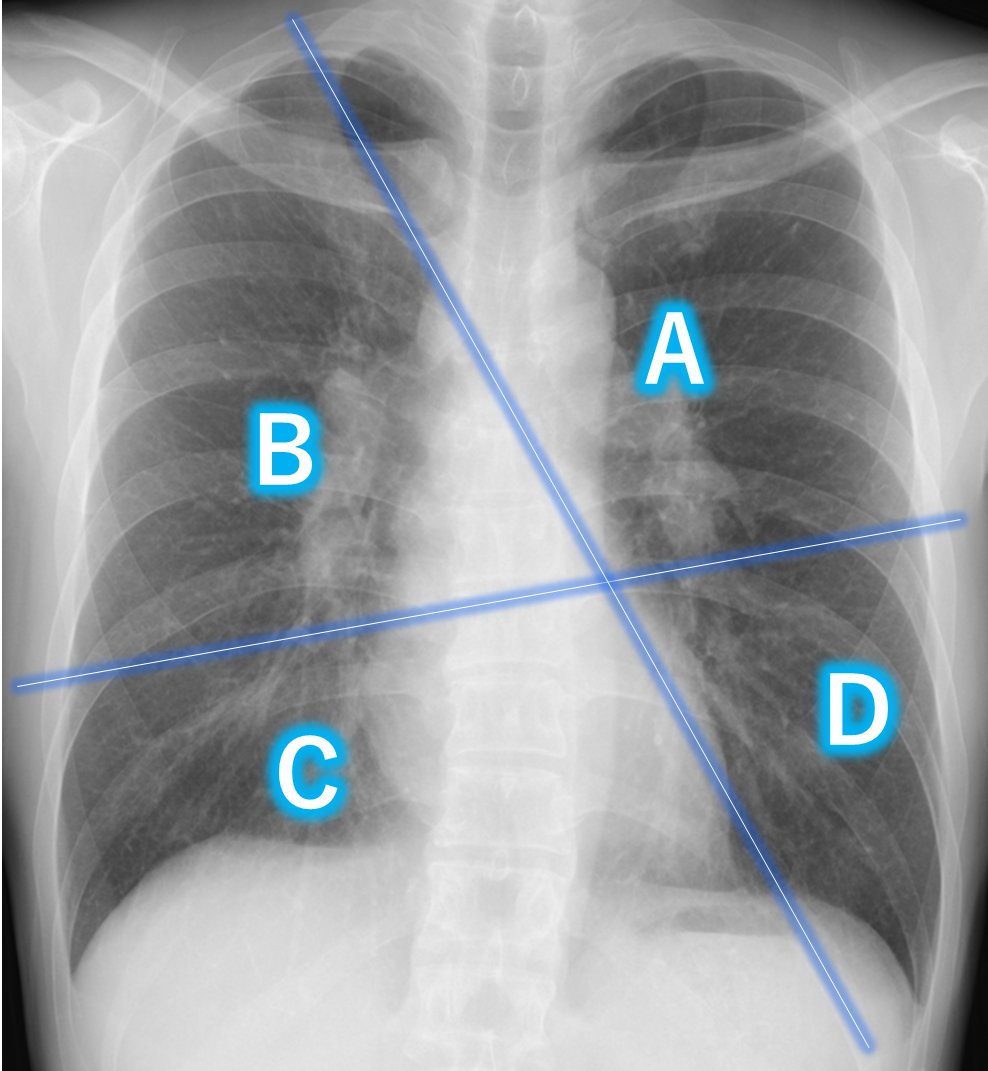

——そして胸部CT——

もろもろ検査→電子タバコの肺障害と診断!